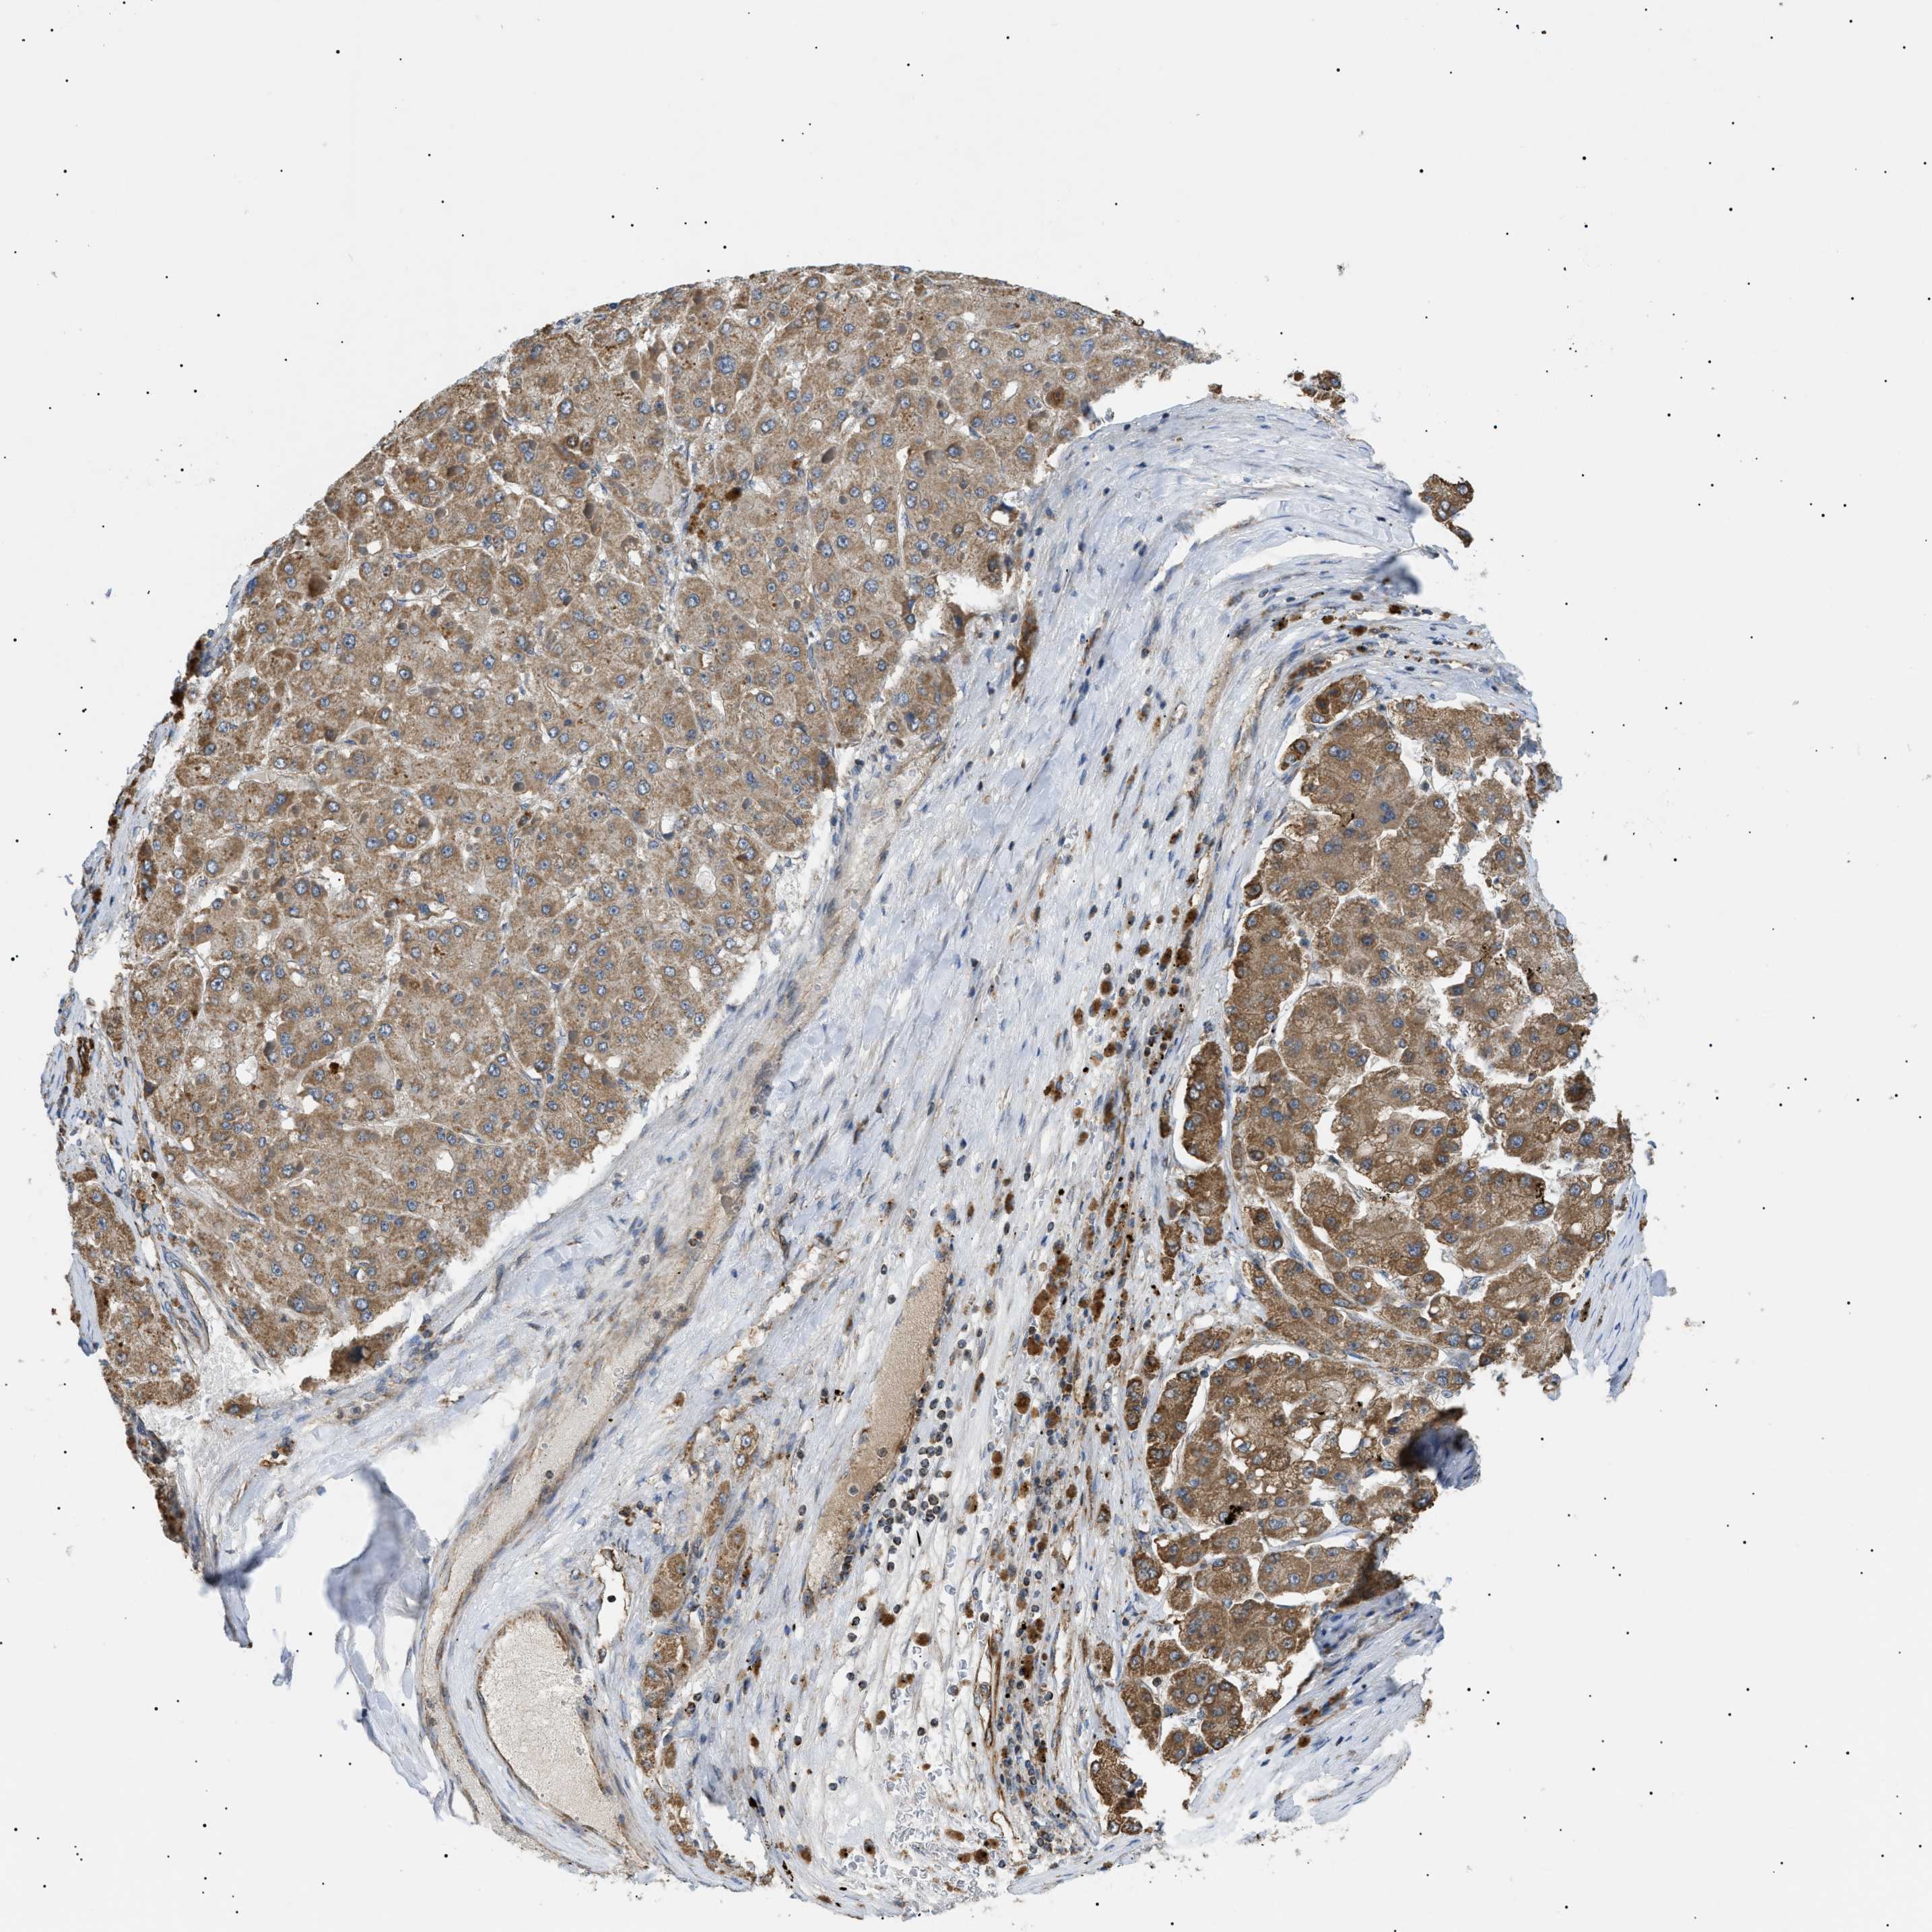

LIVER CANCER - Protein expressioni

A mouse-over function shows sample information and annotation data. Click on an image to view it in a full screen mode. Samples can be filtered based on level of antibody staining by selecting one or several of the following categories: high, medium, low and not detected. The assay and annotation is described here.

Note that samples used for immunohistochemistry by the Human Protein Atlas do not correspond to samples in the TCGA dataset.

Antibody stainingi

Antibody staining in the annotated cell types in the current human tissue is reported as not detected, low, medium, or high, based on conventional immunohistochemistry profiling in selected tissues. This score is based on the combination of the staining intensity and fraction of stained cells.

Each image is clickable and will lead to virtual microscopy that enables deeper exploration of all samples and also displays staining intensity scores, fraction scores and subcellular localization as well as patient and tissue information for each sample.

Antibody HPA016431

Staining

High

Intensity

Strong

Quantity

>75%

Location

Nuclear

Cholangiocarcinoma

Carcinoma, Hepatocellular, NOS